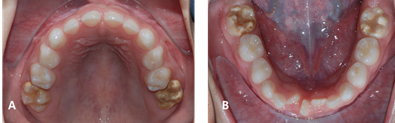

The intraoral clinical examination showed a class III molar relationship, a right posterior crossbite, an edge-to-edge bite, and a permanent supernumerary tooth in the lower incisor region in giroversion (figure 1 ABC). The floor of the mouth, palate, and gums showed no apparent lesions. Dental units (DU) 1.6 and 2.6 exhibited morphological changes with white and yellow-brown opacities in the middle third and on the occlusal surface with diffuse edges, along with post-eruptive fractures in the enamel. Dental units 3.6 and 4.6 had cavity preparations without restorative material on the occlusal-lingual surfaces, which were performed in a private practice around two months ago but became dislodged (figure 2 AB). During thermal tests, the patient displayed sensitivity to cold in DU 1.6, 2.6, 3.6, and 4.6. Dental impressions and a radiographic study were indicated.

There is evidence of mixed dentition in the eruption process, with presence of the permanent teeth germs in their entirety and a supernumerary tooth in the lower incisor area. In the first permanent molars of the maxilla and mandible, enamel density resembling that of dentin is observed (figure 3).

Through clinical and radiographic examination, MIH in the first permanent molars and the presence of a supernumerary in the mandibular incisor region were concluded as a diagnostic impression. The indicated treatment plan is prophylaxis, restoration with ionomeric glass, sealants of pits and fissures in DU 1.6, 2.6, 3.6, 4.6 and topical application of fluoride. Periodic six-monthly check-ups were indicated at the beginning of the treatment to review the restorations for a period of three years. At the age of 10, it was decided to place composite resins. From that date on, visits to the dentist were made annually. Currently, at age 21, the restorations with composite resins that were placed 11 years ago are still in the mouth. They show changes in color and slight wear of the occlusal surface, but the patient does not report any symptoms (figure 4).